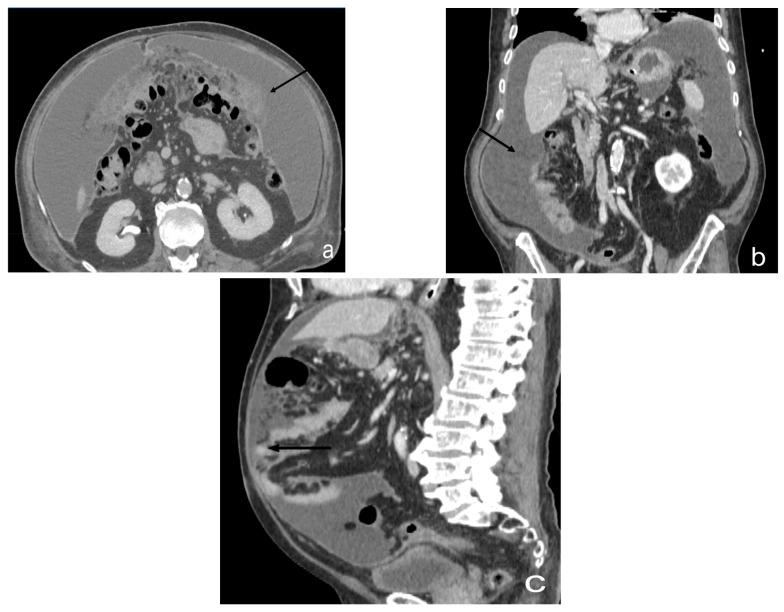

Peritoneal carcinosis is a condition characterized by the spread of cancer cells to the peritoneum, which is the thin membrane that lines the abdominal cavity. It is a serious condition that can result from many different types of cancer, including ovarian, colon, stomach, pancreatic, and appendix cancer. The diagnosis and quantification of lesions in peritoneal carcinosis are critical in the management of patients with the condition, and imaging plays a central role in this process. Radiologists play a vital role in the multidisciplinary management of patients with peritoneal carcinosis. They need to have a thorough understanding of the pathophysiology of the condition, the underlying neoplasms, and the typical imaging findings. In addition, they need to be aware of the differential diagnoses and the advantages and disadvantages of the various imaging methods available. Imaging plays a central role in the diagnosis and quantification of lesions, and radiologists play a critical role in this process. Ultrasound, computed tomography, magnetic resonance, and PET/CT scans are used to diagnose peritoneal carcinosis. Each imaging procedure has advantages and disadvantages, and particular imaging techniques are recommended based on patient conditions. Our aim is to provide knowledge to radiologists regarding appropriate techniques, imaging findings, differential diagnoses, and treatment options. With the advent of AI in oncology, the future of precision medicine appears promising, and the interconnection between structured reporting and AI is likely to improve diagnostic accuracy and treatment outcomes for patients with peritoneal carcinosis.

腹膜癌是一种以癌细胞扩散至腹膜为特征的病症,腹膜是衬于腹腔的一层薄膜。它是一种严重的病症,可由多种不同类型的癌症引发,包括卵巢癌、结肠癌、胃癌、胰腺癌和阑尾癌。腹膜癌中病变的诊断和定量对于该病症患者的管理至关重要,而影像学在这一过程中发挥着核心作用。放射科医生在腹膜癌患者的多学科管理中起着至关重要的作用。他们需要对该病症的病理生理学、潜在肿瘤以及典型的影像学表现有透彻的了解。此外,他们需要知晓鉴别诊断以及各种可用影像学方法的优缺点。影像学在病变的诊断和定量中起着核心作用,放射科医生在这一过程中起着关键作用。超声、计算机断层扫描、磁共振成像和正电子发射断层显像/计算机断层扫描(PET/CT)用于诊断腹膜癌。每种成像检查都有其优缺点,会根据患者情况推荐特定的成像技术。我们的目的是向放射科医生提供有关合适技术、影像学表现、鉴别诊断和治疗方案的知识。随着人工智能在肿瘤学中的出现,精准医学的未来似乎很有前景,结构化报告与人工智能之间的相互联系可能会提高腹膜癌患者的诊断准确性和治疗效果。